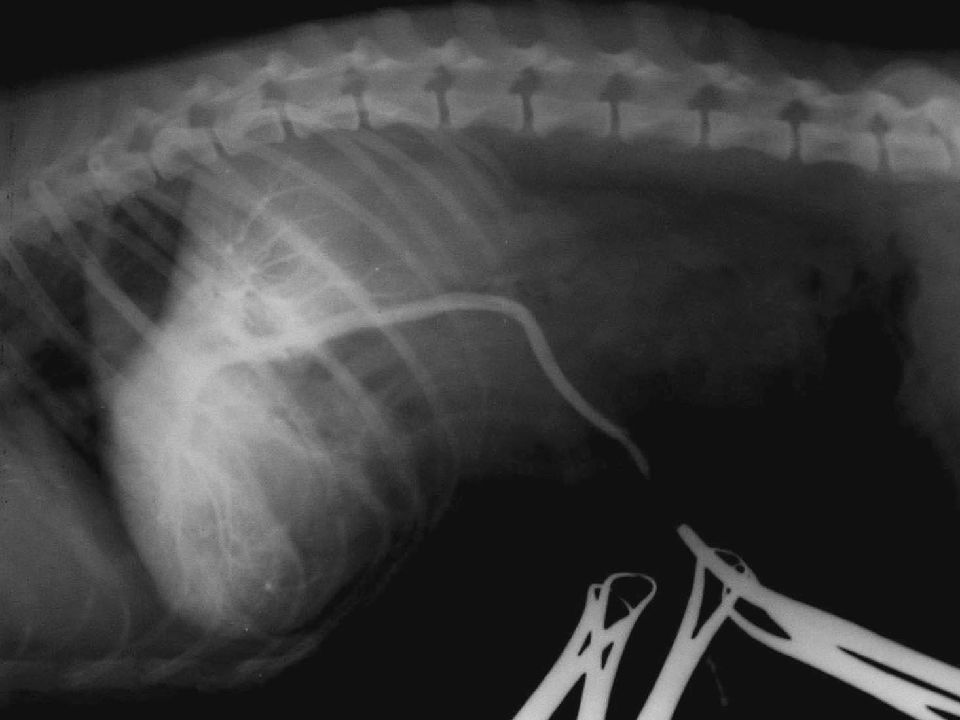

Лечение печеночной недостаточности у собак зависит от причины и степени заболевания. В некоторых случаях может потребоваться хирургическое вмешательство для удаления опухолей или реконструкции заболевших тканей. Кроме того, ветеринар может назначить лекарственную терапию для улучшения функции печени и устранения симптомов. Профилактика также является важной частью лечения, включая соблюдение специальной диеты и избегание воздействия вредных веществ или лекарственных препаратов, которые могут повредить печень собаки.